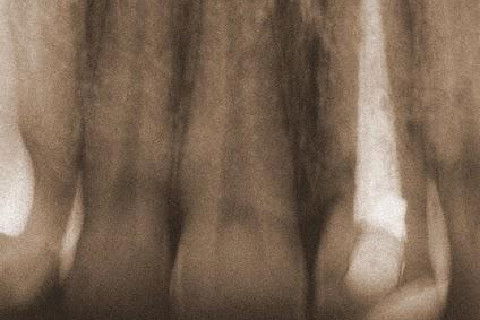

Este CC é continuação deste aqui:

http://www.ident.com.br/aldamarta/caso-clinico/404-reabsorcao-externa-pos-trauma-1o-capitulo

Após todo trabalho para salvar o 21 com RE, o rapaz continuou tomando porrada em brigas, pancadas daqui, pancadas dali e eu remendando o maledeto! :-(

Agora por último (dentro de um fusquinha) bateu com o braço do violão bem no dente!

Nos falamos por telefone e eu lhe expliquei o histórico todo do dente, enviei-lhe o CC por e-mail e lhe pedi que fizesse um trabalho conservador, que oportunamente eu faria uma faceta ou CT em porcelana.